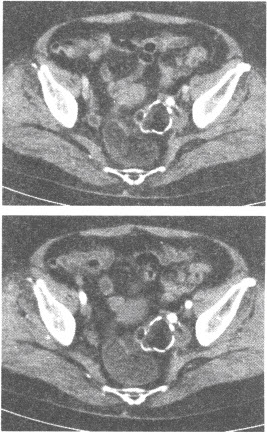

患者,女性,14岁,发现盆腔肿块1个月。查体:腹部膨隆,包块活动度差,叩诊无移动性浊音。B超示盆腔内肿物回声欠均匀,囊实性改变,并见细条状低回声伴声影。

第1题,共3个问题

(单选题)关于该病的描述,正确的是()

A:常伴腹水

B:由脂肪、毛发和液体混合形成低密度区

C:囊性包块中无钙化影

D:常发生种植转移

E:好发于40~50岁

第2题,共3个问题

(单选题)盆腔CT增强扫描图像如下,可诊断为()

A:脂肪瘤

B:肠系膜囊肿

C:卵巢浆液性囊腺瘤

D:卵巢黏液性囊腺瘤

E:卵巢畸胎瘤